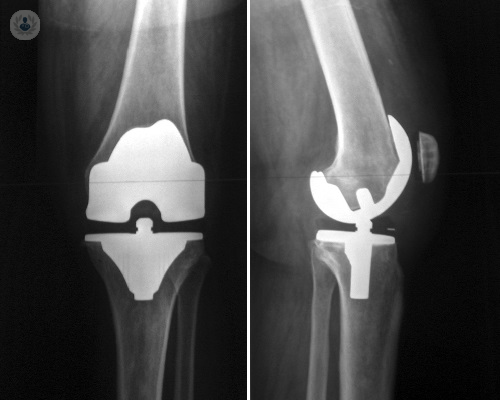

• protesis-de-rodilla

Redacción de Top Doctors

13/10/2017

El protocolo Fast Track en la cirugía protésica de rodilla

El protocolo Fast Track contribuye a la rápida recuperación del paciente que se somete a una cirugía protésica de rodilla. Aplicándolo se consigue que la recuperación sea más rápida y la movilización de la rodilla sea inmediata. Por el Dr. Delgado, experto en Traumatología.